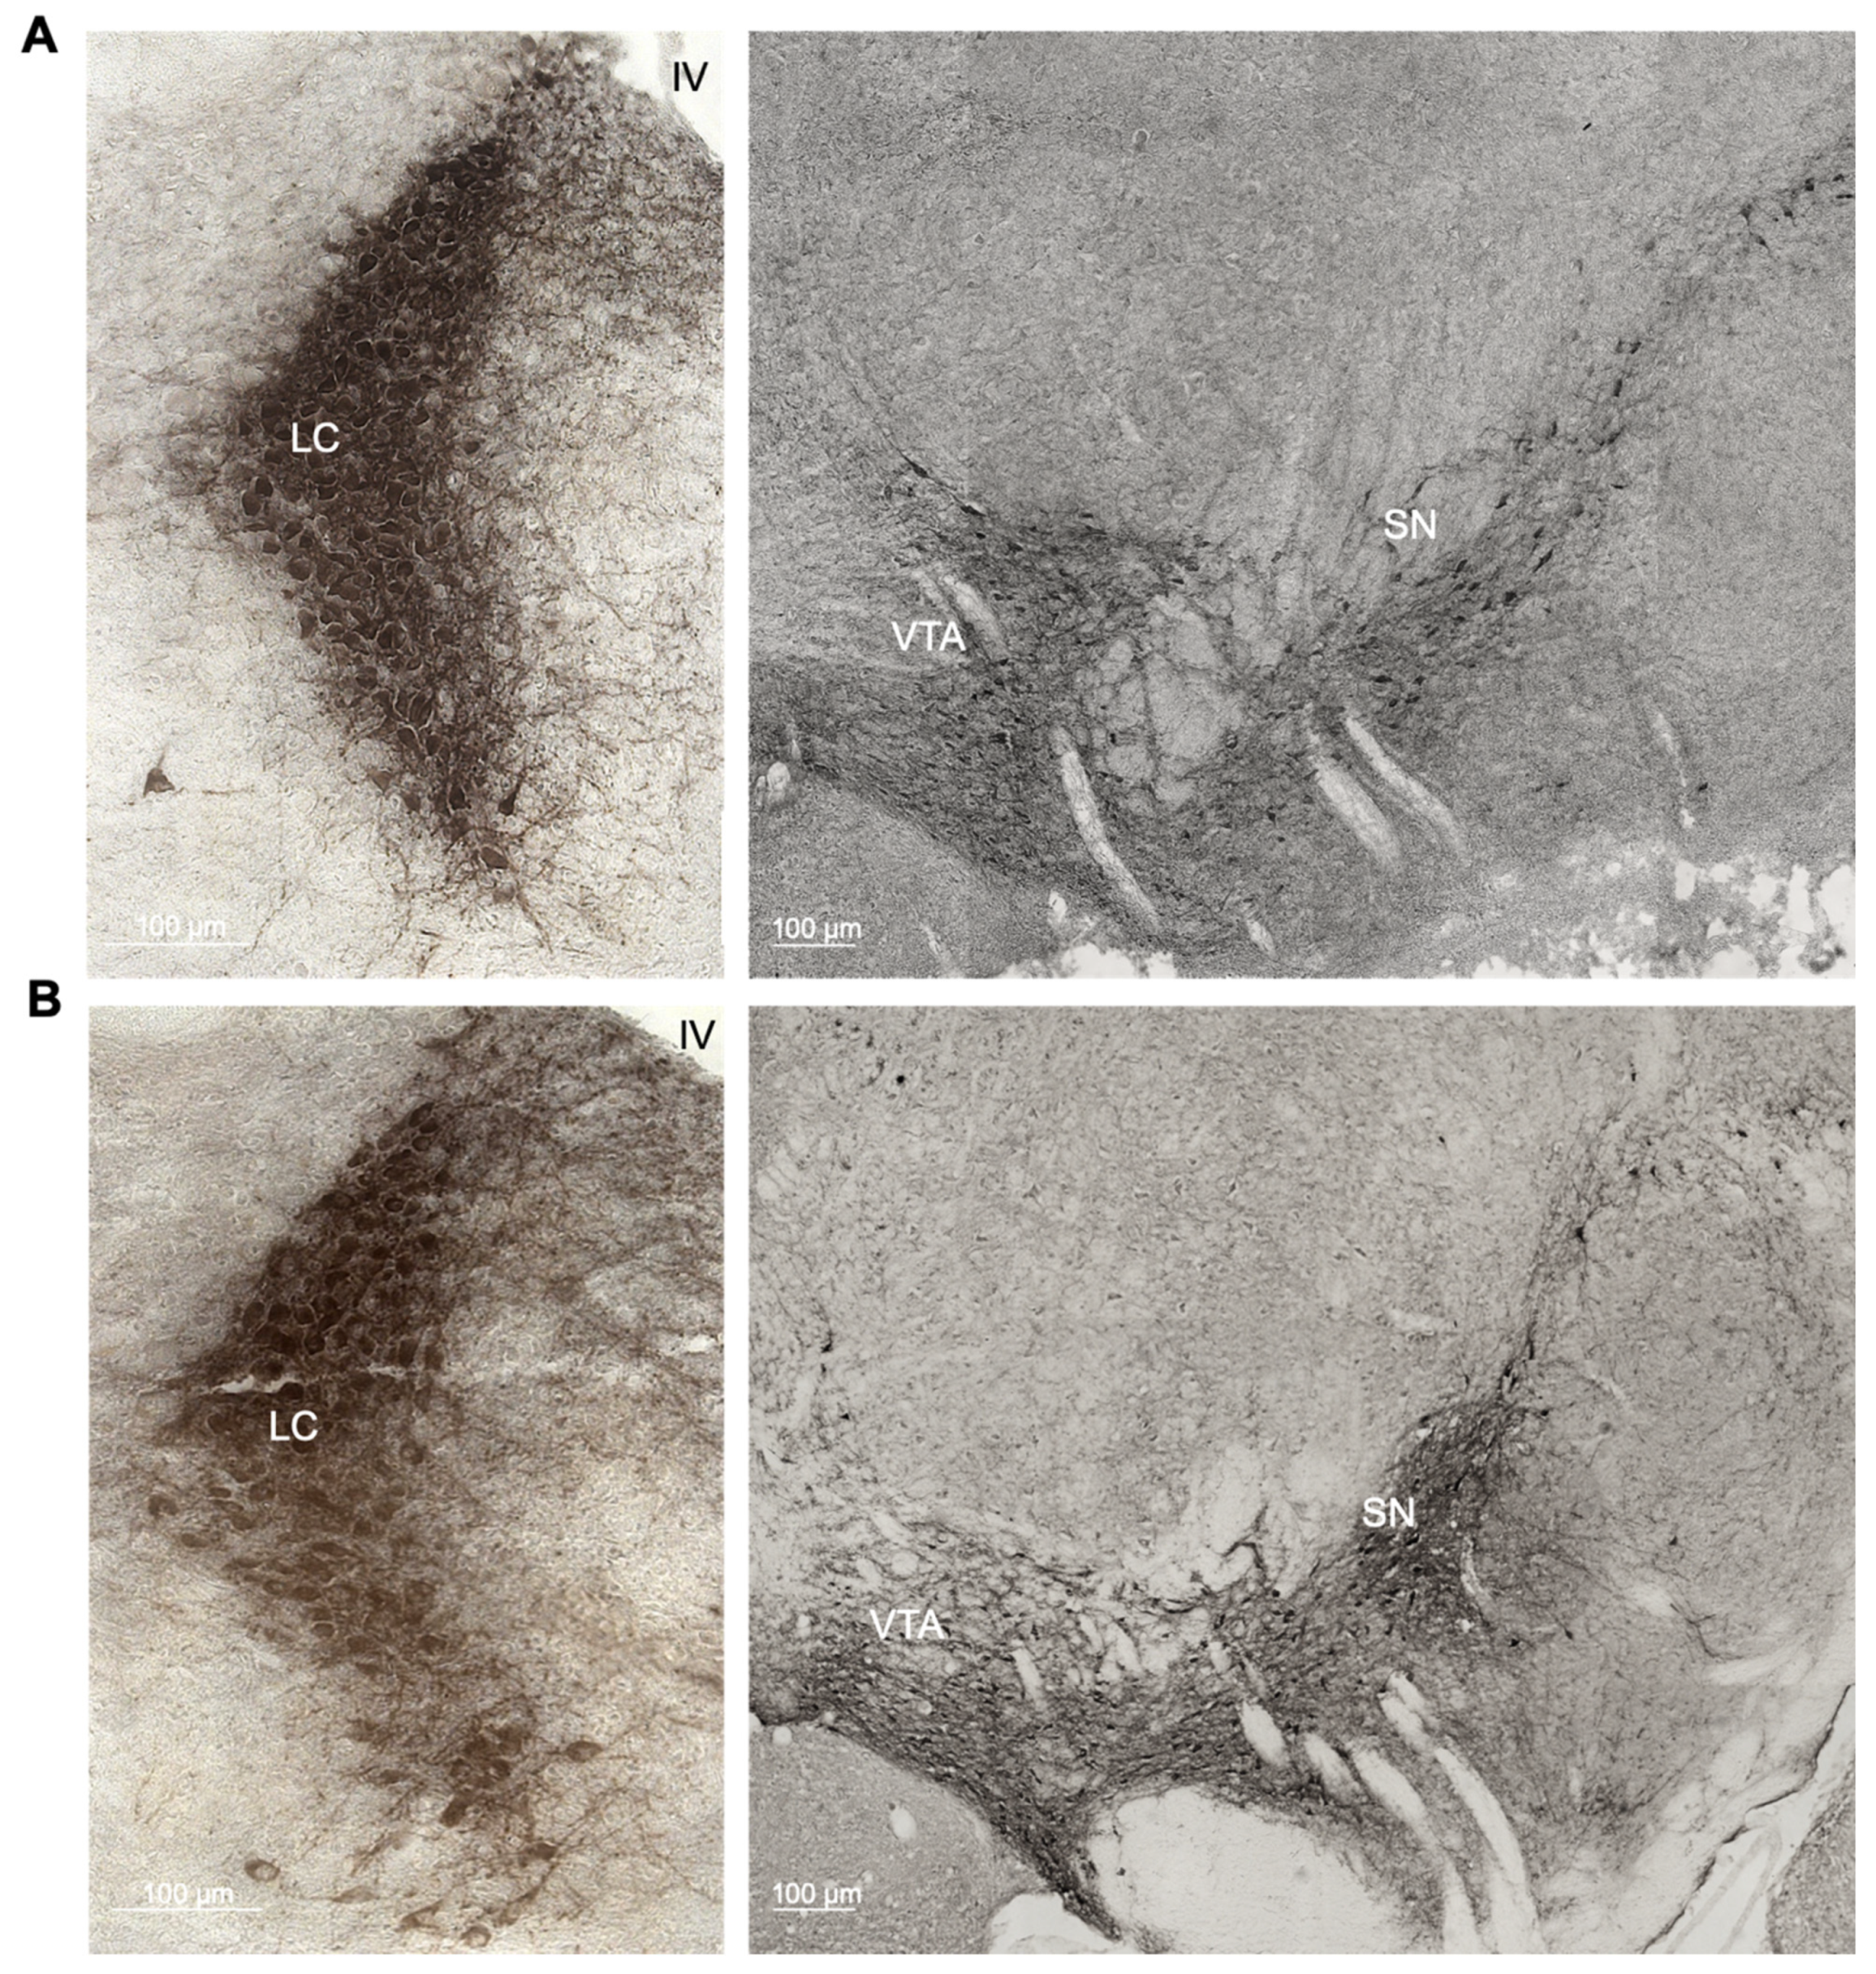

To determine if there is an age-related neuronal loss in the catecholaminergic nuclei in C57BL/6J mice, we compared the number of tyrosine hydroxylase (TH)-positive cells in the locus coeruleus (LC), substantia nigra (SN) and ventral tegmental area (VTA) between 3- (Figure 1A) and 22-month-old wild-type mice by stereological counting (Figure 1B). The number of TH-positive cells in the LC was significantly reduced in old compared to young C57BL/6J mice (t10 = 2.663; p = 0.0238), whereas neither the SN (t12 = 1.425; p = 0.1798) nor the VTA (t12 = 1.483; p = 0.1639) showed significant differences between the age groups (Figure 1C).

Figure 1.

(A,B) Representative photomicrographs of the tyrosine hydroxylase (TH)-positive regions locus coeruleus (LC), substantia nigra (SN) and ventral tegmental area (VTA) in young and old animals. (C) Quantitative stereological analysis of the total number of TH-positive cells of young (3-month-old) and old (22-month-old) C57BL/6J wild-type mice.* p < 0.05 according to Student’s t-test (n = 6–8 per age group). Dots represent single animals, columns represent mean values, and error bars represent standard error of means (SEM).